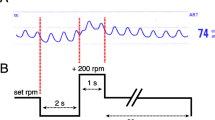

To determine whether AI contributed to refractory low cardiac output syndrome despite CF-LVAD support, a hemodynamic ramp test with simultaneous echocardiography and RHC was performed. Briefly, the patient’s device speed was lowered to 2300 rpm. After 2 min, transthoracic echocardiographic images were obtained and hemodynamic parameters were measured by RHC; the following parameters were recorded: left ventricular end-diastolic dimension (LVEDD), pulmonary capillary wedge pressure (PCWP), and cardiac output (CO). In addition, the following pump parameters were recorded: power, pulsatility index, and pump flow calculated by HVAD monitoring. The device speed was then increased by 200 rpm at 2-min intervals with repeated acquisition of all echocardiographic, RHC, and device parameters at each speed step. The device speed was increased incrementally from 2300 to 3400 rpm. There were no suction events during the hemodynamic ramp test.

Notably, the hemodynamic ramp test revealed only slight reduction in LVEDD for each speed increase of − 0.00081 cm/increment [6], as well as a discrepancy between HVAD pump flow and CO (3.05 vs 3.7 L/min at 2,400 rpm and 3.48 vs 5.7 L/min at 3400 rpm) (Table 1a and Fig. 1a). We presumed that this discrepancy between HVAD pump flow and CO was caused by blood returning to the left ventricle through the insufficient aortic valve. The patient underwent AVR on his 115th day of hospitalization. His symptoms (e.g., shortness of breath, dyspnea on exertion, and pretibial edema) rapidly disappeared. On the patient’s 122nd day of hospitalization, he was successfully weaned off intravenous inotropes. A hemodynamic ramp test conducted after AVR confirmed greater reduction in LVEDD for each speed increase of − 0.14 cm/increment [6], as well as a narrowed gap between HVAD pump flow and CO (Table 1b and Fig. 1b). The patient was discharged uneventfully on his 165th day of hospitalization.

Results of hemodynamic ramp test before and after aortic valve replacement (AVR) (a and b). LVEDD left ventricular end-diastolic diameter, HVAD flow HeartWare continuous-flow left ventricular assist device pump flow calculated by ventricular assist device monitoring, CO cardiac output calculated by right heart catheterization, PCWP pulmonary capillary wedge pressure, rpm rotations per minute